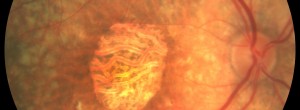

Feeder vessel laser photocoagulation for idiopathic, subfoveal polypoidal choroidal vasculopaty not responding to eithelial growth factor therapy or photodynamic therapy